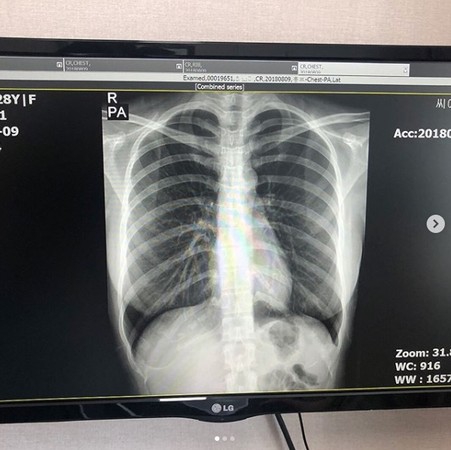

韩国网红Choi Somi同时拥有甜美外型、火辣身材,立体五官与外貌,更被指神似台湾第一网红郭雪芙。不过,人红是非多的她,过去频频遭质疑隆胸,眼见谣言如雪球般越滚越大,近日她直接在社交网站上晒出胸部X光照及诊断书,用行动证明身材有料是纯天然的。